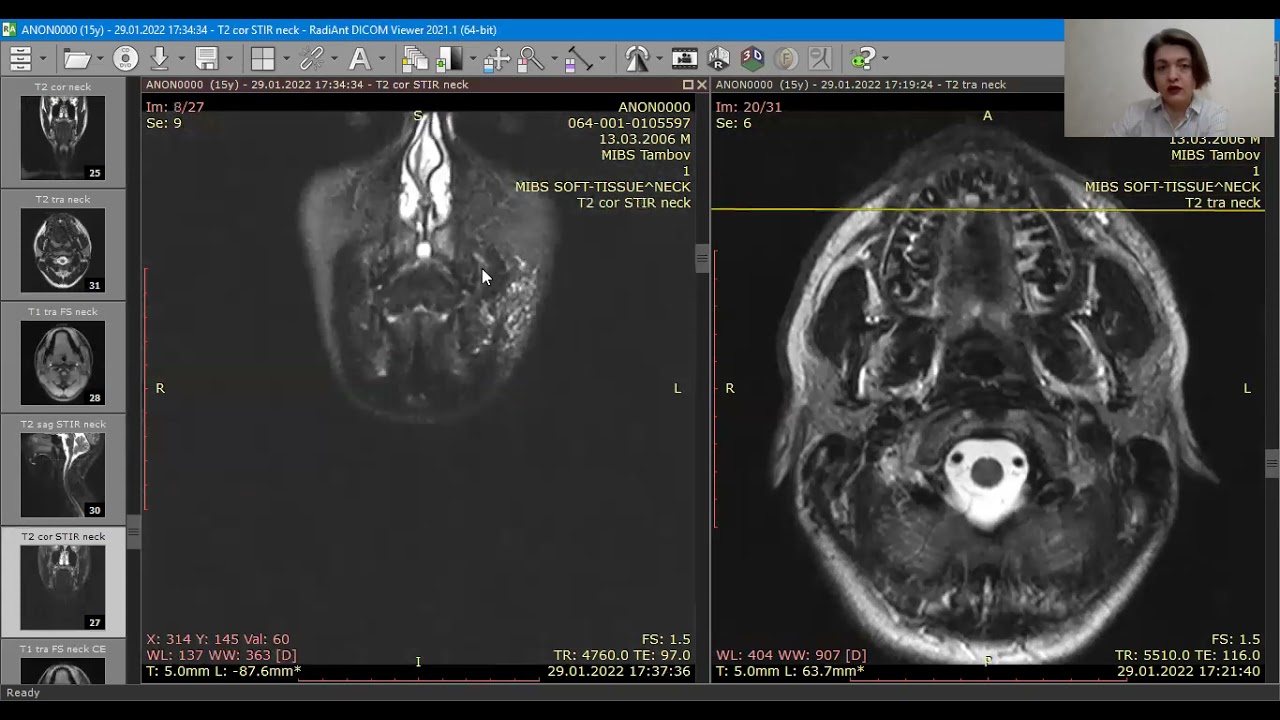

Что покажут снимки МРТ шеи у ребенка с лимфангиомой

- Заполненное жидкостью образование хорошо визуализируется на Т2-взвешенных изображениях

- Интенсивность сигнала на Т1-взвешенных изображениях зависит от содержания белка и наличия кровоизлияний

- Возможен уровень жидкости в пределах кисты (кровоизлияние)

- Отсутствие определяемого кровотока

- Умеренное контрастное усиление перегородок

- Имеется объемный эффект.

МРТ в режиме подавления сигнала от жидкости. Лимфангиома (стрелки) имеет гиперинтенсивный сигнал. Окологлоточный компонент опухоли смещает и сдавливает просвет глотки.